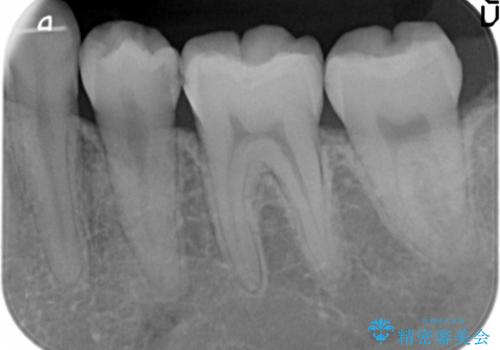

- 奥歯の歯と歯の間が虫歯になっていました。

セラミックインレーで治療しました。

虫歯が進行して、神経に近くなると、冷たいものが染みたりする神経症状が出てきます。

そういった自覚症状が出る前に処置することをおすすめします。